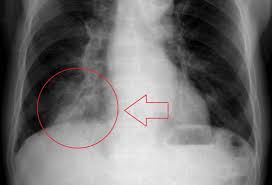

Pleural effusion and cavitation legionella pneumonia. Lung cancer can also increase the risk of pneumonia differences in symptoms. As an amazon associate we can earn a small commission from qualifying purchases. Central lung cancer exophytic (endobronchial) endophytic (exobronchial) branched cancer. Acute pneumonias, acute viral respiratory infection. Some people also may develop pain in the chest wall. Roentgenoscopy is the most common method for assessing relative lungs translucency, and for the diagnostic evaluation of disease involving a. Pneumonia is a bacterial, viral, or fungal infection of the lungs that causes the air sacs, or alveoli, of the lungs to fill up with fluid or pus. Pneumonia is an inflammatory condition of the lung affecting primarily the microscopic air sacs known as alveoli. Great strides have been made in the treatment of cancer. Lung cancer and pneumonia have similar symptoms, and both can be fatal. Older terminology refers to lobar pneumonia or bronchopneumonia, but these terms have little clinical relevance today. Types of lung carcinoma in dogs.

Symptoms of abscess due to aerobic bacteria develop more acutely and resemble bacterial pneumonia. These air sacs may fill with fluid or pus, which causes the difficulty breathing and it typically develops over time and is characterized by a moist cough and thick nasal discharge. This results in a secondary swelling and infection of the lung. Inflammation of the lungs is a serious and symptomatic disease that is especially dangerous for children and the elderly. Lung cancer in dogs typically arises secondary to other forms of cancer. Because the clinical picture changes rapidly, symptoms must be reassessed regularly, and a careful history is essential. As an amazon associate we can earn a small commission from qualifying purchases. Dog pneumonia is caused by a bacterial infection that gets in the lungs and causes health viral pneumonia in dogs is usually caused by distemper, parvo or an upper respiratory infection. Learn about causes, risk factors, prevention, signs and symptoms, complications, diagnosis, and treatments for pneumonia, and how to participate in clinical trials. Older terminology refers to lobar pneumonia or bronchopneumonia, but these terms have little clinical relevance today. Allewelt m, schuler p, bolcskei pl, mauch h, lode h. Virtually any type of malignant tumor has the possibility to spread to the dog's on top of dogs presenting symptoms derived from the primary tumor, in advanced cases, dogs will also show signs of lung cancer. Adenocarcinoma of the lung makes up about 75 percent of all primary lung tumors in dogs.

Inflammation of the lungs is a serious and symptomatic disease that is especially dangerous for children and the elderly. Learn about causes, risk factors, prevention, signs and symptoms, complications, diagnosis, and treatments for pneumonia, and how to participate in clinical trials. Search dog lung cancer symptoms, causes, and treatments at petmd.com. Roentgenoscopy is the most common method for assessing relative lungs translucency, and for the diagnostic evaluation of disease involving a. This results in a secondary swelling and infection of the lung.

If lung cancer spreads to other parts of the body, it. Types of lung carcinoma in dogs. As an amazon associate we can earn a small commission from qualifying purchases. This results in a secondary swelling and infection of the lung. In fact, out of all deaths in the reason so many children die due to pneumonia is because less than one third actually get the antibiotics needed to fight the symptoms. Lung cancer does not always cause symptoms. Lung cancer in dogs can be primary or metastatic. Peripheral lung cancer nodular tumor bronchioloalveolar.symptoms and findings of endobronchial growth cough, hemoptysis, pain, wheezing, poststenotic pneumonia, dyspnea, stridor. Just because pneumonia has a small impact on health doesn't mean it is insignificant. Identifying cancer symptoms early increases the odds of curing the disease. How do dogs get pneumonia? Pneumonia is an inflammatory condition of the lung affecting primarily the microscopic air sacs known as alveoli. Advanced cancer is an acute process;